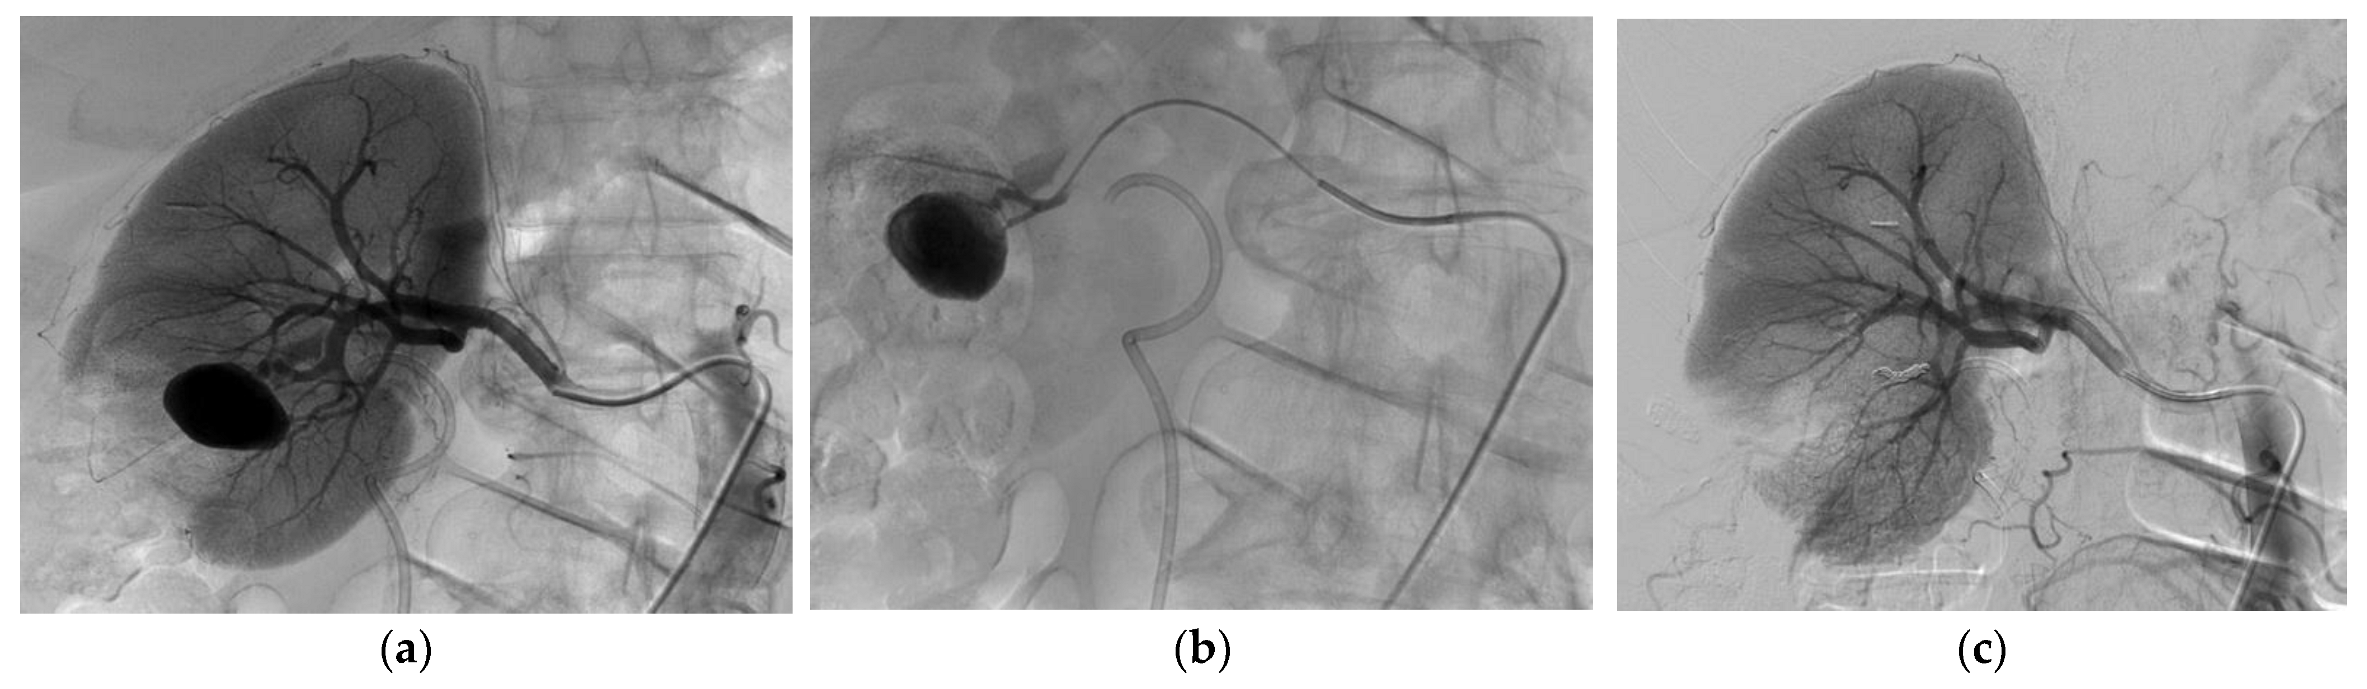

3.2. Endovascular Treatment

| Iatrogenic vascular lesion | |

| Number of renal false arterial aneurysms | 47 |

| Number of renal arteriovenous fistulas | 9 |

| Number of patients with both | 7 (28%) |

| Aneurysm size (mm) | 10.5 (±4.7) |

| Embolization technique | |

| Coils | 8 (32%) |

| Liquid embolic agent | 8 (6 Glubran2, 1 Onyx, 1 Gelatispon) (32%) |

| Coils and liquid embolic agent | 9 (36%) |

| Technical success at first attempt | 24 (96%) |

| Technical success at first or second attempt | 25 (100%) |

| Clinical success, one attempt | 24 (96%) |

| Clinical success, one or two attempts | 25 (100%) |